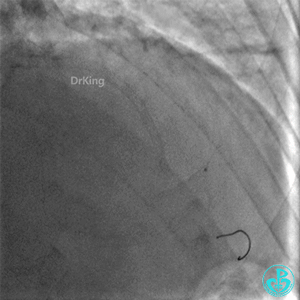

撤回逆向导丝及微导管造影,钝缘支远端侧支造影剂渗漏,局部造影剂滞留范围不断扩大。

明胶在血管怎么降解并发症丨前降支CTO同侧逆向开通时侧支血管破裂,弹簧圈联合明胶海绵封堵_https://www.jmylbn.com_新闻资讯_第31张

明胶在血管怎么降解并发症丨前降支CTO同侧逆向开通时侧支血管破裂,弹簧圈联合明胶海绵封堵_https://www.jmylbn.com_新闻资讯_第32张

前降支末梢经微导管释放3.0×2.5mm弹簧圈封堵破口。